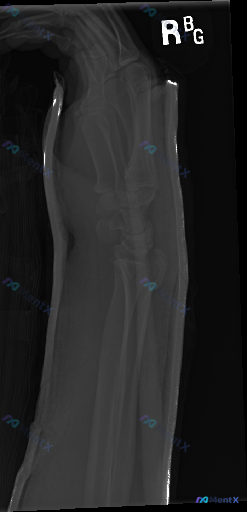

整理到一张放射影像资料,是右侧前臂X光片(正位)。 想请大家先读片,看看这张片子里有没有明确的异常?如果有,你认为最核心、最需要优先关注的是哪一组表现? (注:背景信息暂时先不放,就单看这张影像的表现来讨论)

整理到一份右侧前臂X光正位影像的病例资料,先和大家同步目前可见的表现: 1. 骨骼方面:桡骨远端干骺端区域可见骨皮质中断,远折端有向背侧/桡侧移位的迹象;尺骨茎突处也有骨皮质不连续的表现。 2. 关节方面:桡腕关节的正常解剖关系似乎有改变,下尺桡关节区域看起来间隙不太规整。 3. 软组织:桡骨远端周...

整理到一张右侧前臂侧位X光片的影像资料,大家可以先看看这些表现: 1. 桡骨远端骨干骺端可见骨皮质中断,骨折线通过,伴有背侧成角移位及粉碎性改变 2. 尺骨茎突也有骨皮质中断 3. 腕关节背侧及掌侧有明显软组织肿胀 4. 肘关节对合关系良好,尺桡骨中段皮质连续 5. 骨质密度分布均匀,未见明显骨质溶...